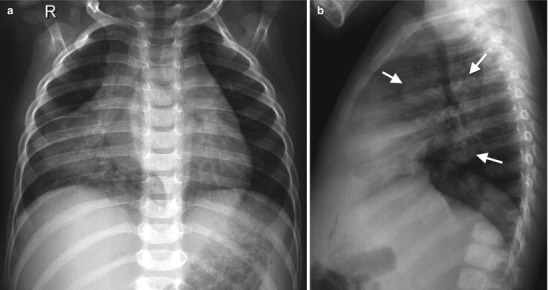

Lymphadenopathy (present in 92 %) with or without a visible Ghon focus is the radiographic hallmark of TB infection and usually involves the hilar and paratracheal regions. The Ghon focus may be too small to be radiographically visible but can also undergo caseation and calcify (Fig. 13.17). Disease progression may occur at the site of Ghon focus, within the regional lymph nodes, or following disease spread (Fig. 13.18). Parenchymal involvement in primary pulmonary TB most commonly appears as homogeneous consolidation, although it can appear patchy, linear, nodular, and mass-like. Caseation necrosis, liquefaction, or calcifications can be seen within the consolidation and can progress into extensive lung damage (Marais et al. 2004) (Fig. 13.19). Enlarged and edematous hilar, paratracheal, and subcarinal lymph nodes may cause compression of the adjacent bronchus and can lead to hyperinflation or atelectasis of the affected lung segment. Contrast-enhanced CT shows a characteristic appearance consisting of central areas of low attenuation with peripheral rim enhancement and obliteration of perinodal fat (Kim et al. 1997) (Fig. 13.20).

Fig. 13.18.

Primary TB disease. Chest radiographs of a 2-year-old girl with chronic cough and fever showing dense right middle lobe consolidation on the frontal view (a) and extensive lymphadenopathy (white arrows) on the lateral view (b)